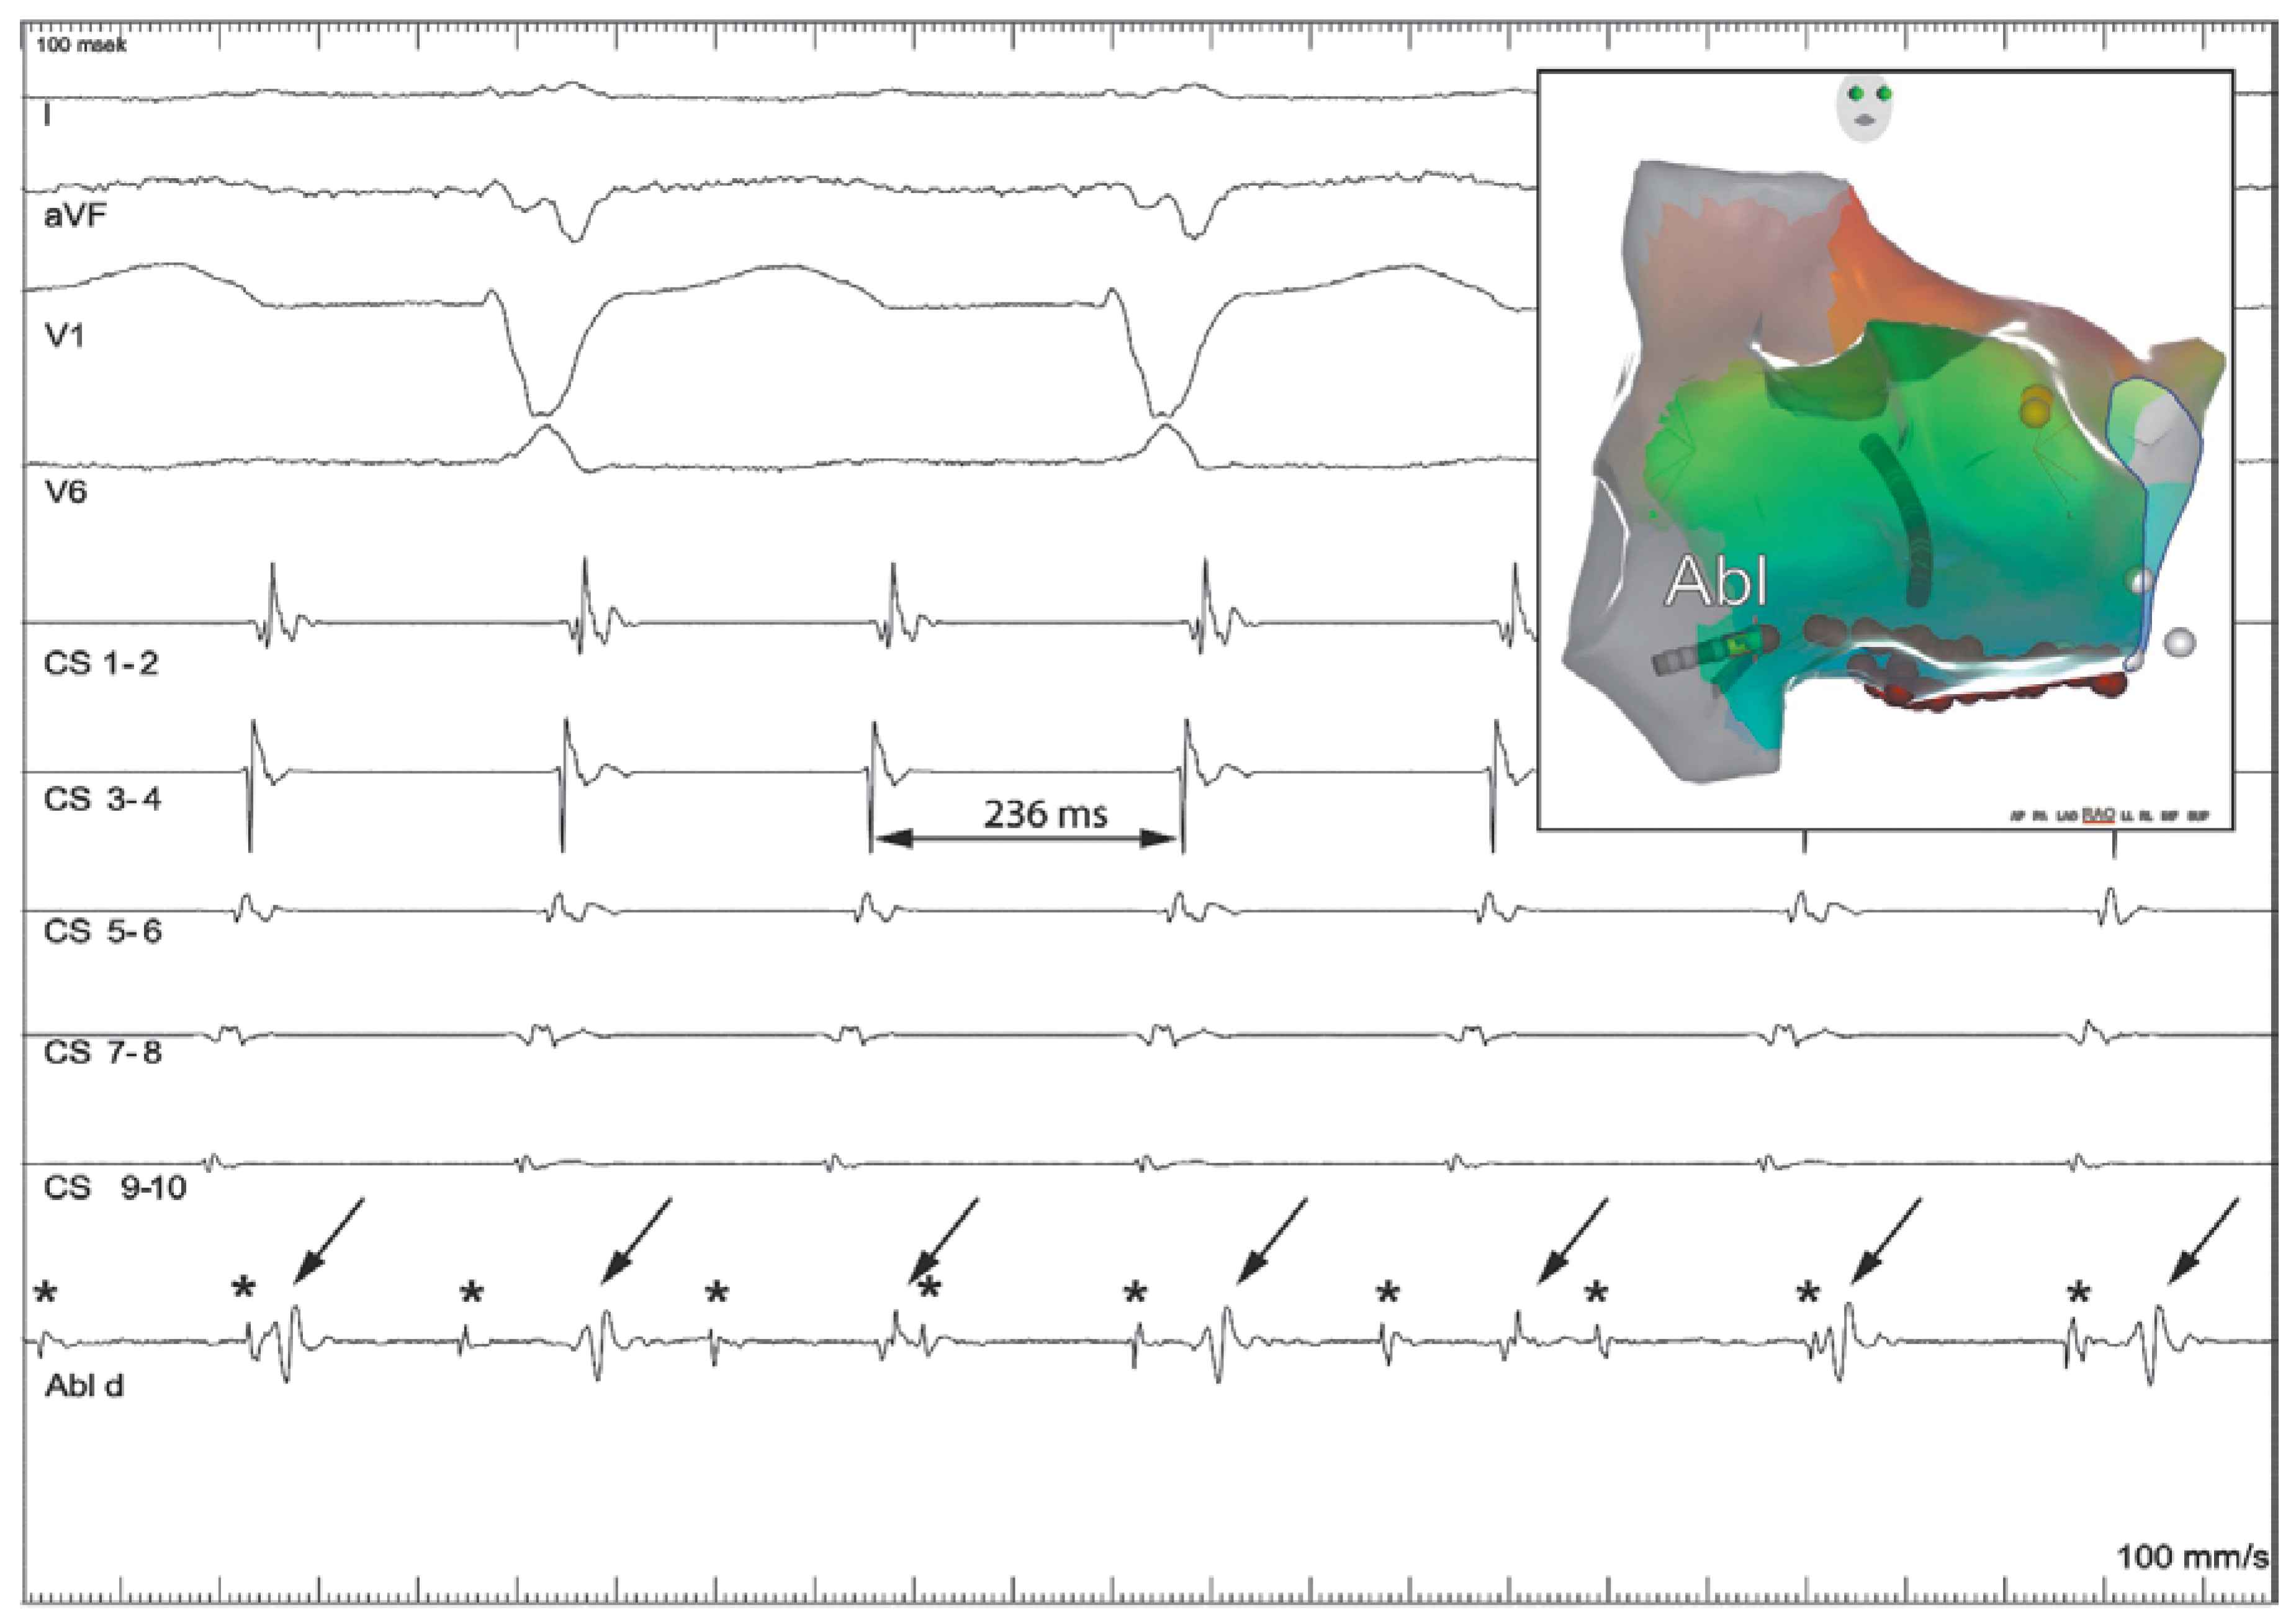

Dual Tachycardia Involving the Cavotricuspid Isthmus and Eustachian Ridge

Case report